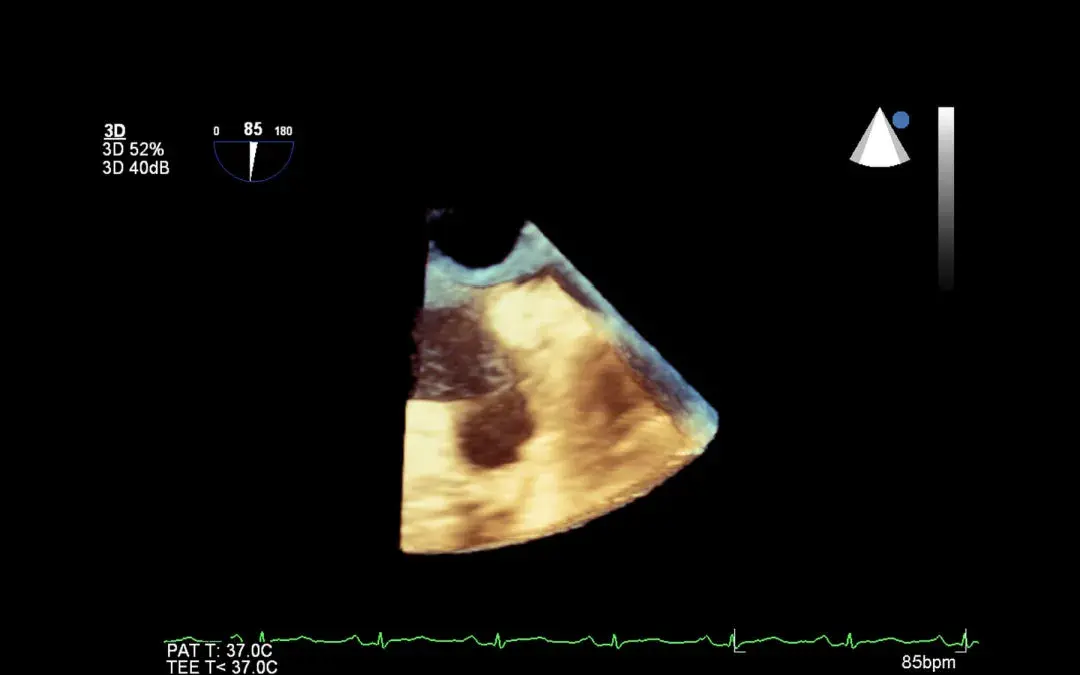

A 3D echo test is a non-invasive medical test that creates a three-dimensional image of your heart using sound waves. The test is also called a 3D echocardiogram or simply an ED echo. The 3D echo test produces more detailed images in real-time than traditional 2D echocardiograms, allowing doctors to examine the heart’s structure, function, and blood flow more accurately.

What does a 3D echo show?

A 3D echo shows

- Detailed images of the heart’s structure and blood flow

- Heart’s size and shape, the thickness of its walls, and how well it pumps blood

- Heart valves and blood vessels, blockages, leaks, or other narrowed blood vessels

A 3D echo test helps produce detailed images of the structure, function, and blood flow of the heart. It can reveal the size and shape of the heart, the thickness of its walls, and how well it pumps blood. It can also detect heart valve problems, congenital heart defects, and blood vessel blockages or narrowing in the blood vessels. You must prepare for the test by following your doctor’s instructions and informing them of any allergies or medical conditions that may affect the accuracy of the test.